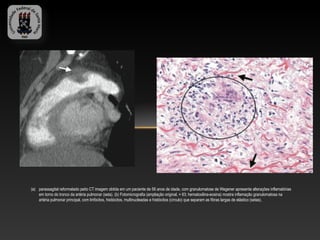

(a) parassagital reformatado peito CT imagem obtida em um paciente de 56 anos de idade, com granulomatose de Wegener apresenta alterações inflamatórias

em torno do tronco da artéria pulmonar (seta). (b) Fotomicrografia (ampliação original, × 63; hematoxilina-eosina) mostra inflamação granulomatosa na

artéria pulmonar principal, com linfócitos, histiócitos, multinucleadas e histiócitos (círculo) que separam as fibras largas de elástico (setas).